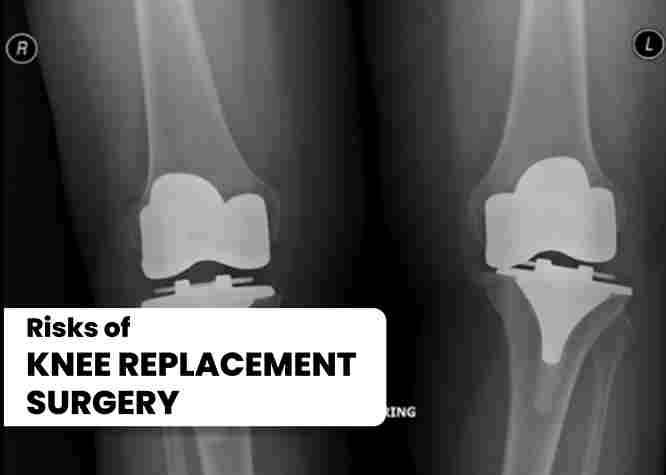

Risks of Knee Replacement Surgery

Knee replacement surgery, like any surgery, carries some risks. Some of the risks associated with knee replacement surgery include:

1. Infection: There is a risk of infection after knee replacement surgery, which can be treated with antibiotics.

2. Blood Clots: Blood clots can form in the legs after knee replacement surgery, which can be prevented with blood thinners and compression stockings.

3. Nerve Damage: There is a risk of nerve damage during knee replacement surgery, which can cause numbness, tingling, or weakness in the legs.

4. Loosening or Dislocation of the Implant: The artificial knee joint can loosen or dislocate over time, which may require revision surgery.